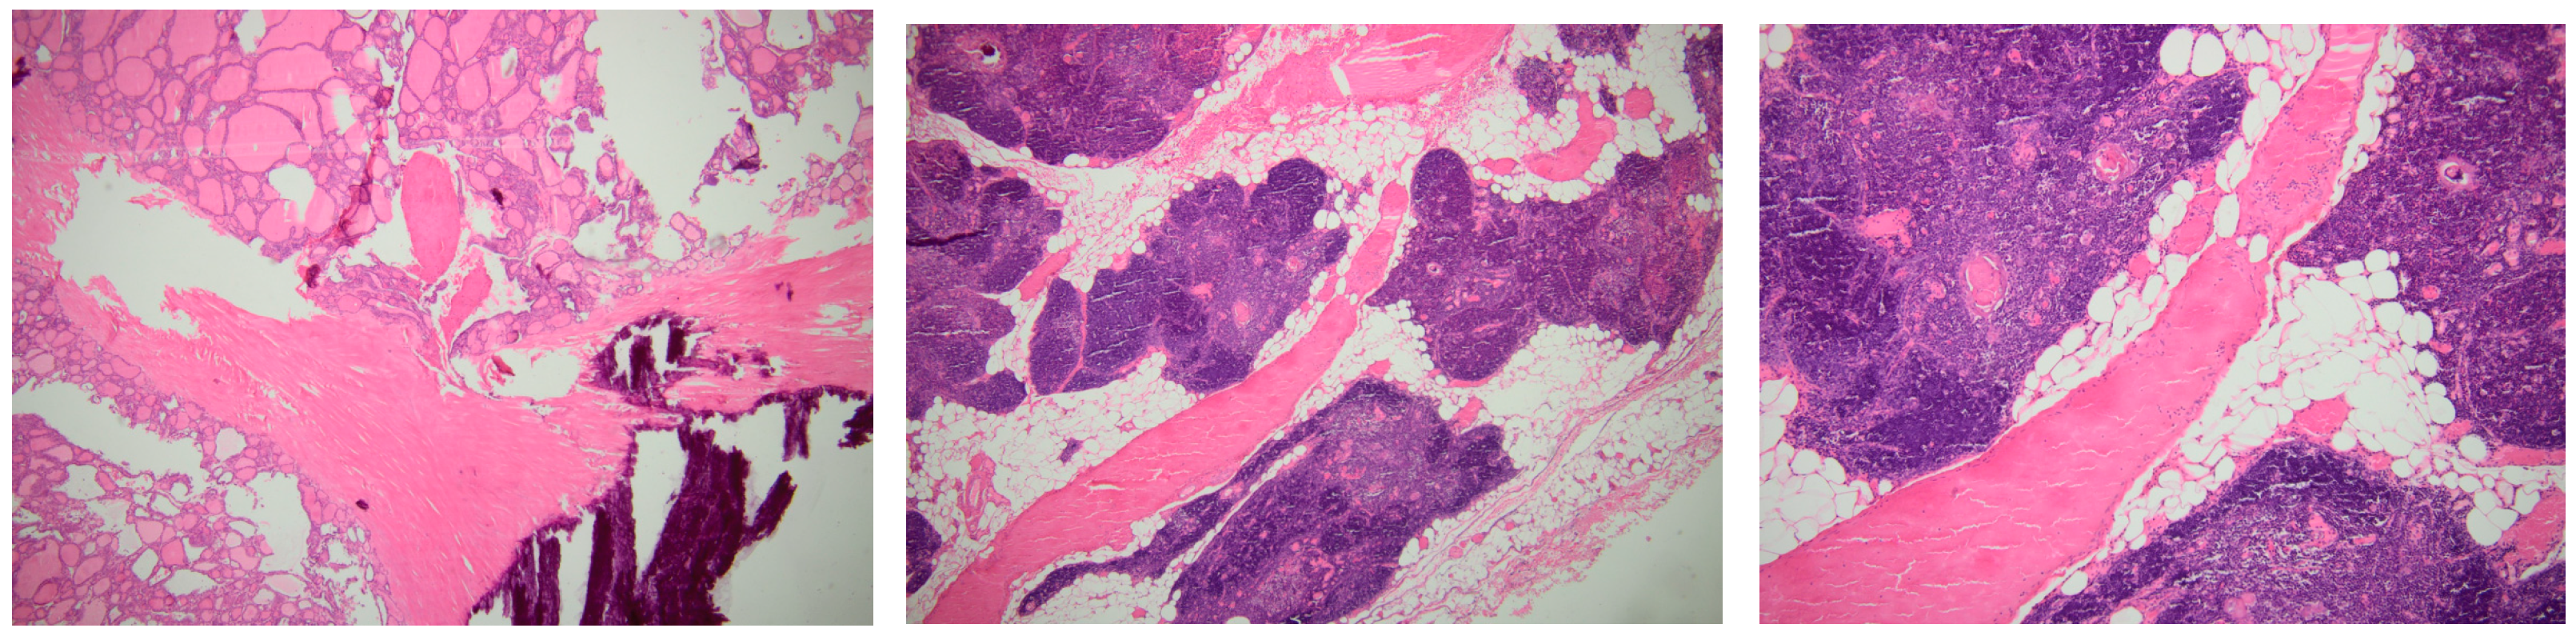

3.3. Post-Operatory Check-Up

- The eutopic thyroid presented with a micro-nodular pattern, which was not considered a malignancy; that is why a fine needle aspiration was not performed before surgery, and an indication of a concurrent thyroidectomy was not established [80];

- While serum thyroglobulin remains a valuable tumour marker upon the resection of thyroid malignancy originating from follicular cells [83], in cases with benign conditions, as seen here, its role is minor.